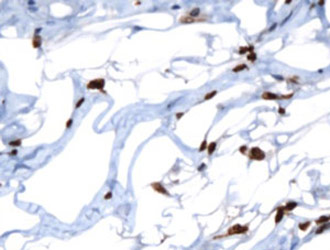

SOX-10

SOX-10 est un marqueur très sensible pour les mélanomes (97% contre 91% pour le S-100). Il est particulièrement sensible pour les mélanomes desmoplastiques qui sont souvent difficiles à détecter par d’autres marqueurs de mélanocytes. SOX-10 est modérément à fortement exprimée dans les mélanomes...